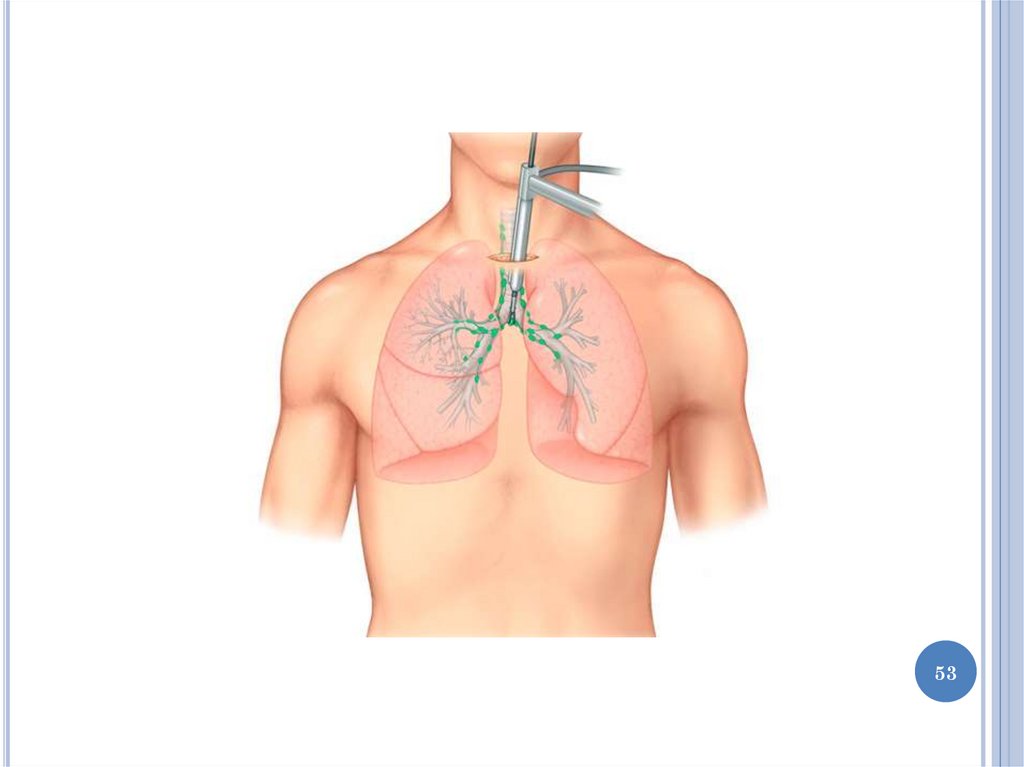

54.

ТОРАКОСКОПИЯ

Торакоскопия – эндоскопический метод

исследования полости плевры пациента. Метод

манипуляции заключается во введении специального

инструмента через пункцию в стенке грудной клетки.

Четкая цветная визуализация на экране позволяет

врачу оценивать состояние легких, органов

средостения и перикарда, находящихся в полости

серозной оболочки. Процедура, выполняющаяся

только в больничных условиях, используется как для

установки точного диагноза, так и в терапевтических

целях.